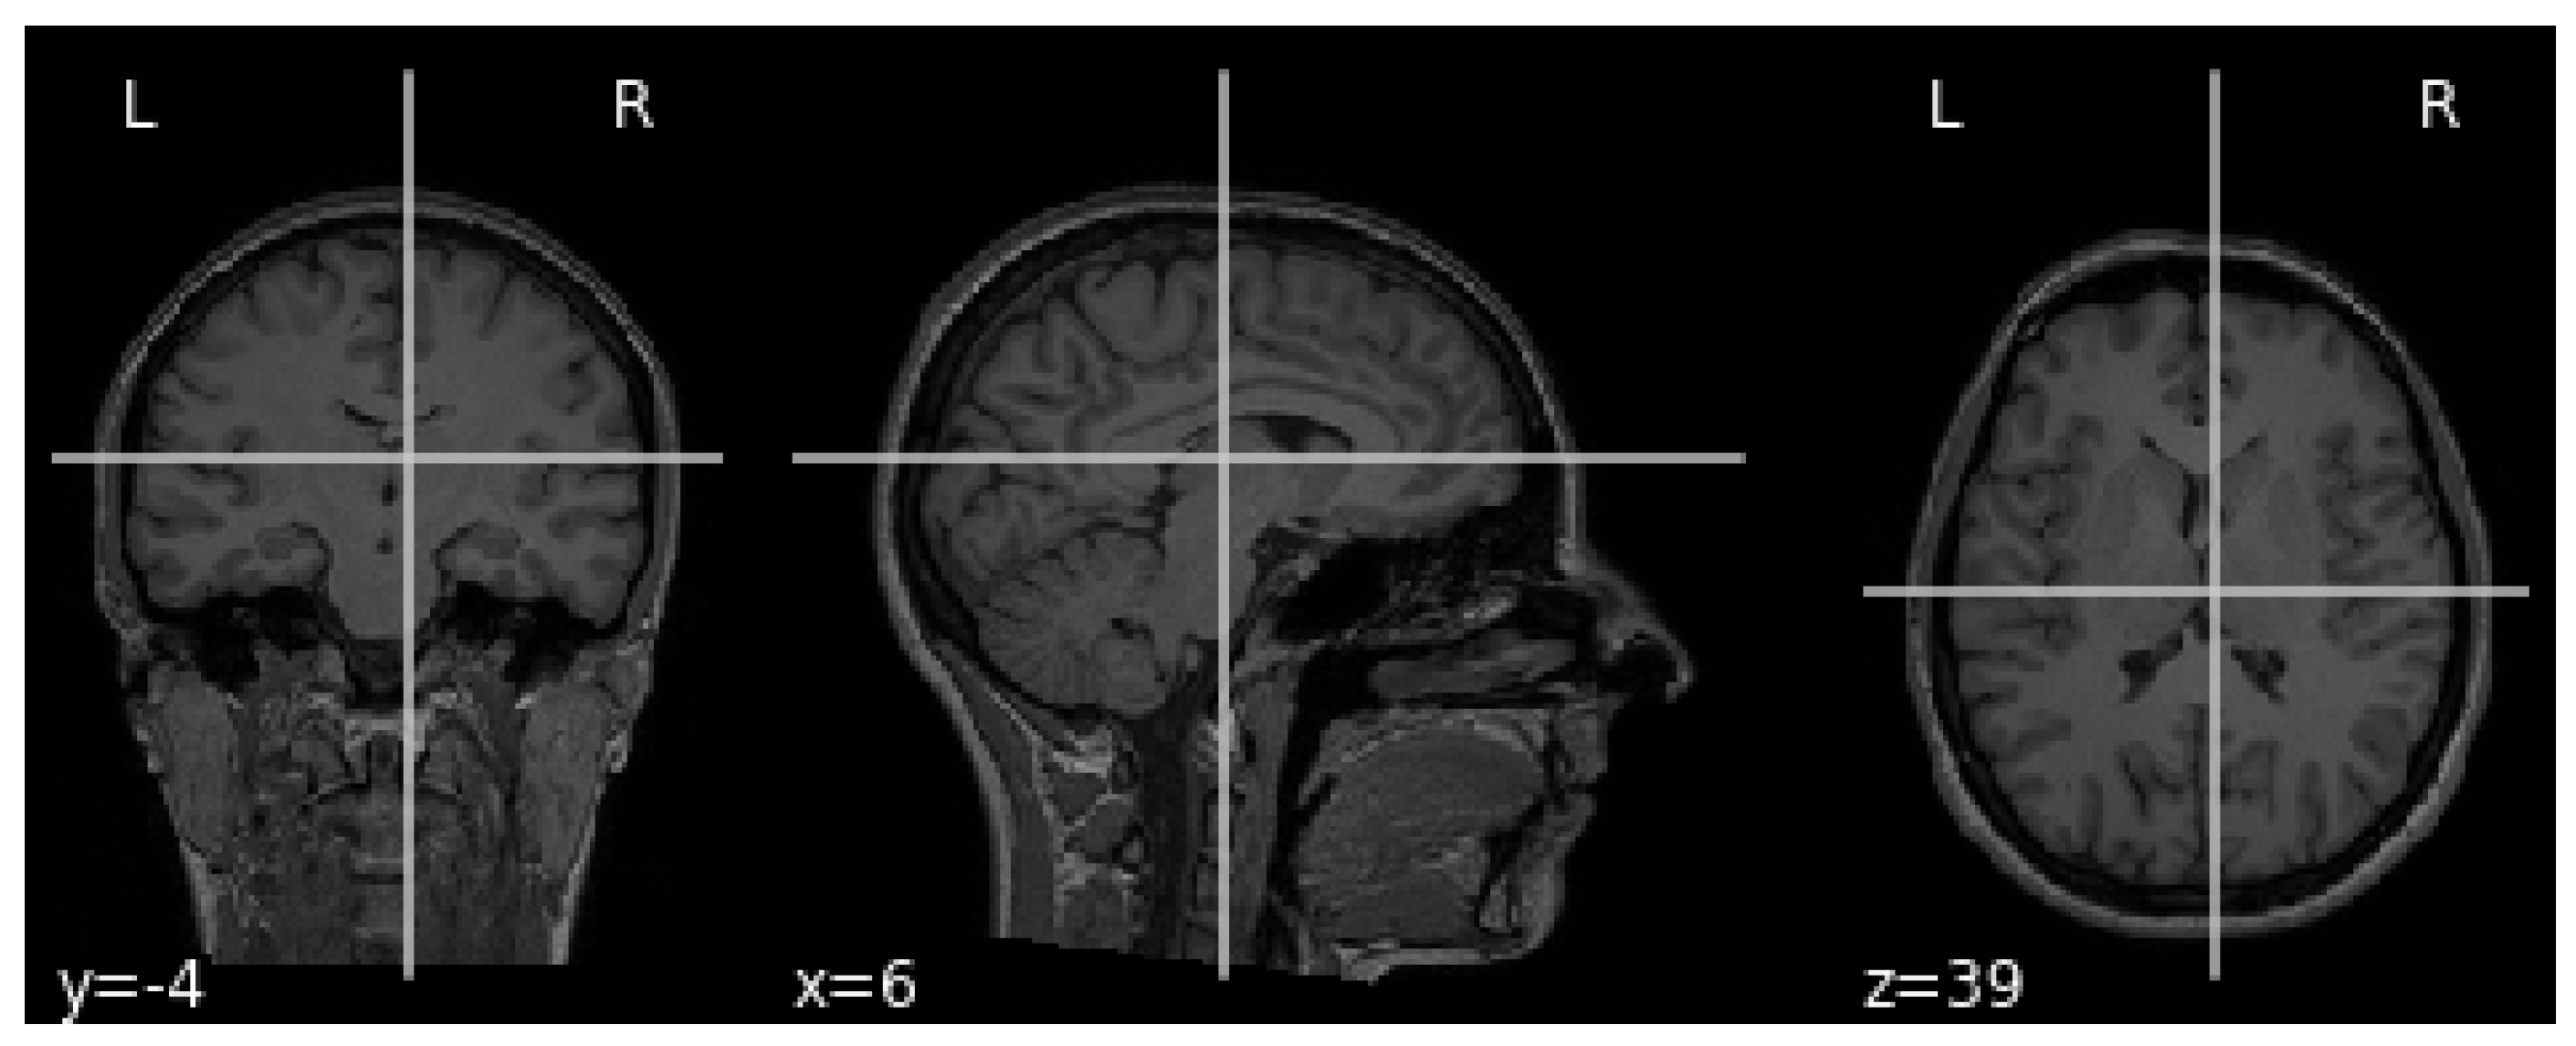

The MRI requires the setup of specific parameters, including radio-frequency pulse and gradient. T1 and T2 sequences are usually used in practice, with both providing specific information about the observed tissue. This research uses the T1 sequence. To reduce the amount of images required for the healthy brain, six sections were chosen from MRI images. A healthy brain sample is shown in Figure 3.